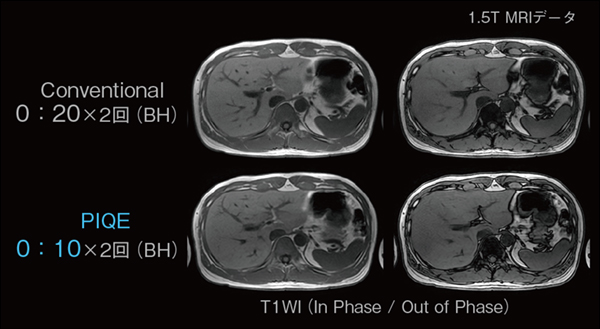

■息止め時間短縮の例

腹部の撮像では,検査時間短縮のために息止め下で撮像をする場合も多い。息止め時間は,患者の負担軽減および画質の安定性を考慮し,可能なかぎり短いことが望まれる。撮像時間を短縮するための手段の一つとして,データ収集時に位相マトリックス数を減らす方法があるが,空間分解能が低下するという問題が生じる。PIQEを用いた画像再構成によりマトリックス数を増やすことができるため,空間分解能を維持しつつ,撮像時間を短縮することが可能である(図2)。

図2 PIQEによる撮像時間短縮の例